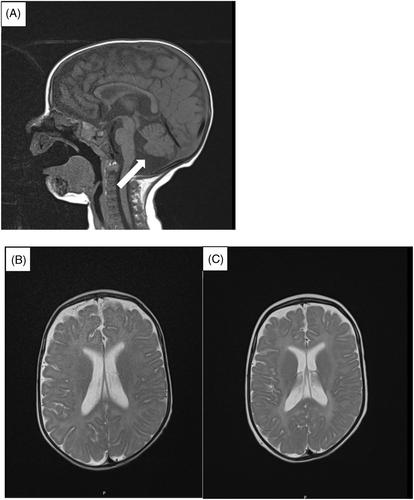

胡普克-布伦德尔综合征(Huppke-Brendel Syndrome,HBS)是一种常染色体隐性遗传疾病,由乙酰-CoA 转运体-1(AT-1)的编码基因 SLC33A1 突变引起。迄今为止,已有九名儿童患者和一名成人患者患上了这种疾病。组氨酸铜的治疗试验未能取得任何临床改善。在此,我们描述了两名新患者的临床特征,其中一名患者是通过基因分析确诊的,他的兄弟姐妹是根据临床特征在死后确诊的。我们展示了其中一名患者的乙酰化治疗试验,包括 N-乙酰半胱氨酸和生酮饮食。我们提供了治疗前后脑脊液(CSF)和血浆中 N-乙酰化氨基酸的生化数据。我们的结果表明,生酮饮食和 N-乙酰半胱氨酸似乎并不能使 CSF 或血浆中的 N-乙酰化氨基酸浓度恢复正常。总体代谢模式表明,N-乙酰化氨基酸在脑脊液中的水平呈下降趋势,在血浆中的下降程度较小。虽然有一些假设,但 AT-1 的功能仍不明确,需要进一步研究才能更好地了解这种复杂疾病的机制。

Huppke–Brendel syndrome (HBS) is an autosomal recessive disorder caused by SLC33A1 mutations, a gene coding for the acetyl-CoA transporter-1 (AT-1). So far it has been described in nine pediatric and one adult patient. Therapeutic trials with copper histidinate failed to achieve any clinical improvement. Here, we describe the clinical characteristics of two novel patients, one of them diagnosed by gene analysis and his sib postmortally based on clinical characteristics. We demonstrate a therapeutic trial with acetylation therapy, consisting of N-acetylcysteine and ketogenic diet, in one of them. We provide biochemical data on N-acetylated amino acids in cerebrospinal fluid (CSF) and plasma before and after starting this treatment regimen. Our results indicate that ketogenic diet and N-acetylcysteine do not seem to normalize the concentrations of N-acetylated amino acids in CSF or plasma. The overall metabolic pattern shows a trend toward lowered levels of N-acetylated amino acids in CSF and to a lesser extent in plasma. Although there are some assumptions, the function of AT-1 is still not clear and further studies are needed to better understand mechanisms underlying this complex disorder.